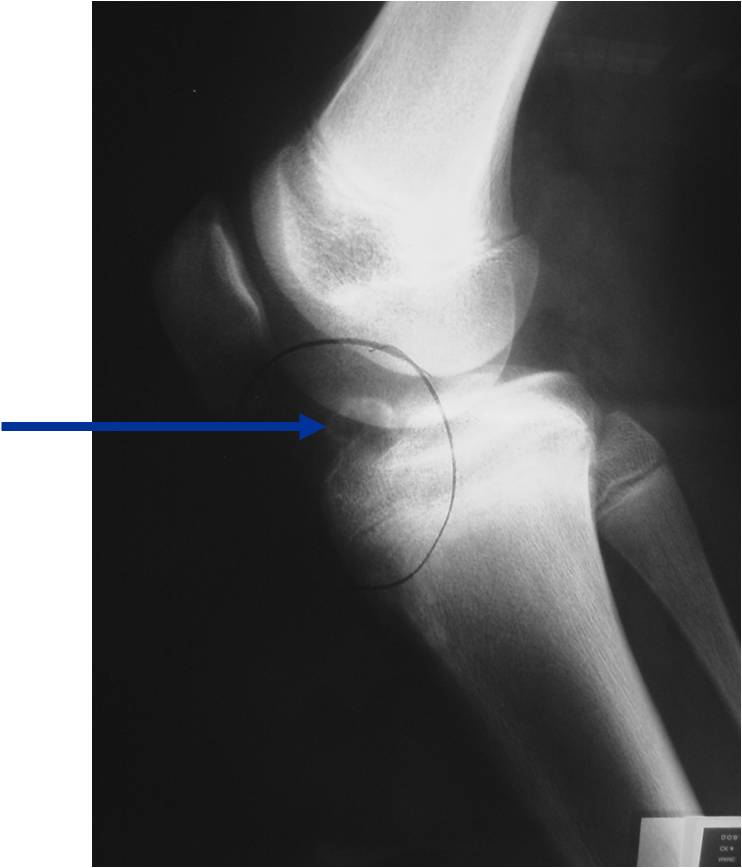

General Information Enchondroma is a benign indolent intramedullary hyaline cartilage neoplasm Accounts for 10% of all benign osseous tumors Limited growth, most lesions are less than 5 cm in maximal dimension Bones grow from a cartilaginous growth plate that...